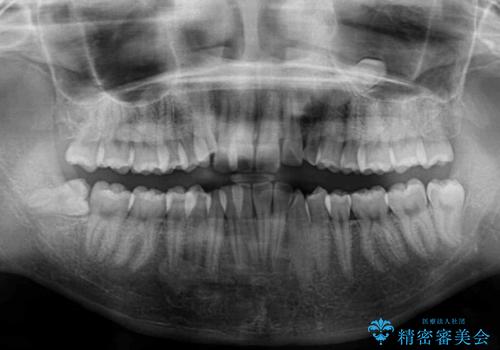

- 前歯のデコボコと残っている乳歯の部分へのインプラント治療を希望して来院された患者様です。

当初は目立たない上下裏側矯正を希望されていましたが、歯並びの悪さによる磨き残しが多く、歯肉炎が認められたため、より清潔な環境で治療を進められるインビザラインを選択することとしました。

前歯のデコボコが強かったため、上の奥歯を後方に動かす量が多くなり、結果として2年以上の治療期間を擁することとなりました。